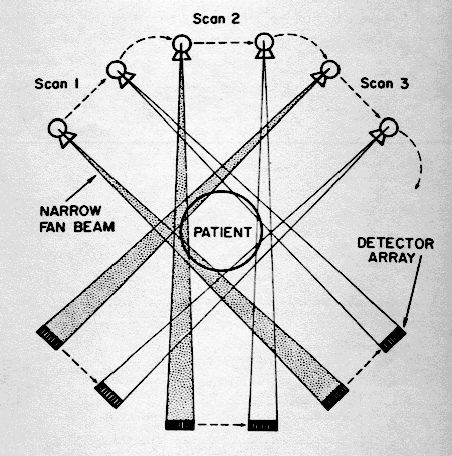

SEGUNDA GENERACIÓN

• Traslación y rotación

• 10-30 detectores

• Haz de RX en abanico

• Adquisición en 2.5 min